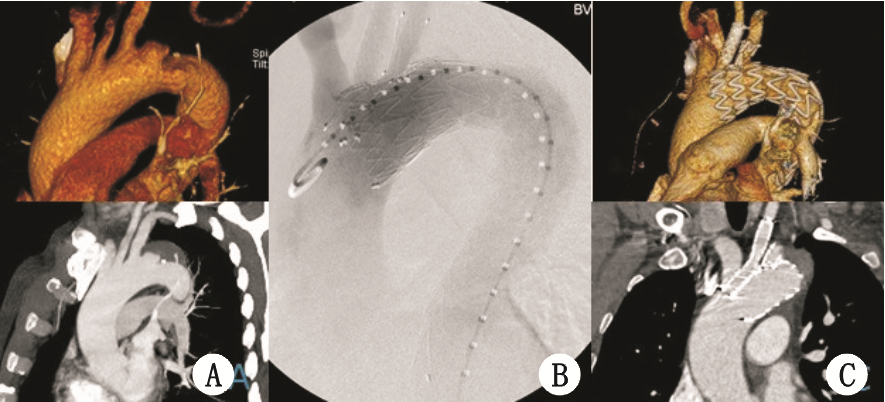

| A:对照组;B:ALI组 图 3 病例3,A:术前CTA可见弓部累及LSA局限性夹层,LSA和LCCA距离 < 0.5 cm;B:术中单分支支架和LCCA烟囱支架释放后造影;C:术后12个月随访CTA,单分支支架和烟囱支架通畅,支架形态良好,无内漏,血管重构良好 |

所有患者均一期手术成功,支架主体定位精确,烟囱支架位置形态好,术后造影无明显狭窄。未发生死亡、脑梗死、肾功能不全等围手术期严重并发症,术后造影穿透性溃疡封闭良好,夹层近端破口被封堵,未见明显内漏。随访期间,无患者死亡。随访12~18个月,随访CTA显示:支架形态良好,无明显移位,主动脉壁间血肿被吸收,术后6个月随访1例左锁骨下动脉分支支架在左锁骨下动脉开口处狭窄约40%,12个月随访时无明显改变(图 1 C箭头),进一步随访中;其余2例分支支架通畅无狭窄扭曲,3例患者均未见明显内漏(图 1-3 )。1例左颈总烟囱支架术后6个月随访时,被主体支架压迫烟囱支架使颈总开口处狭窄(图 2C,D),术后12个月随访时在颈总动脉开口处血栓形成闭塞(图 2E,F),无头晕、脑梗等颅内缺血表现,未做特殊处理,继续随访中。